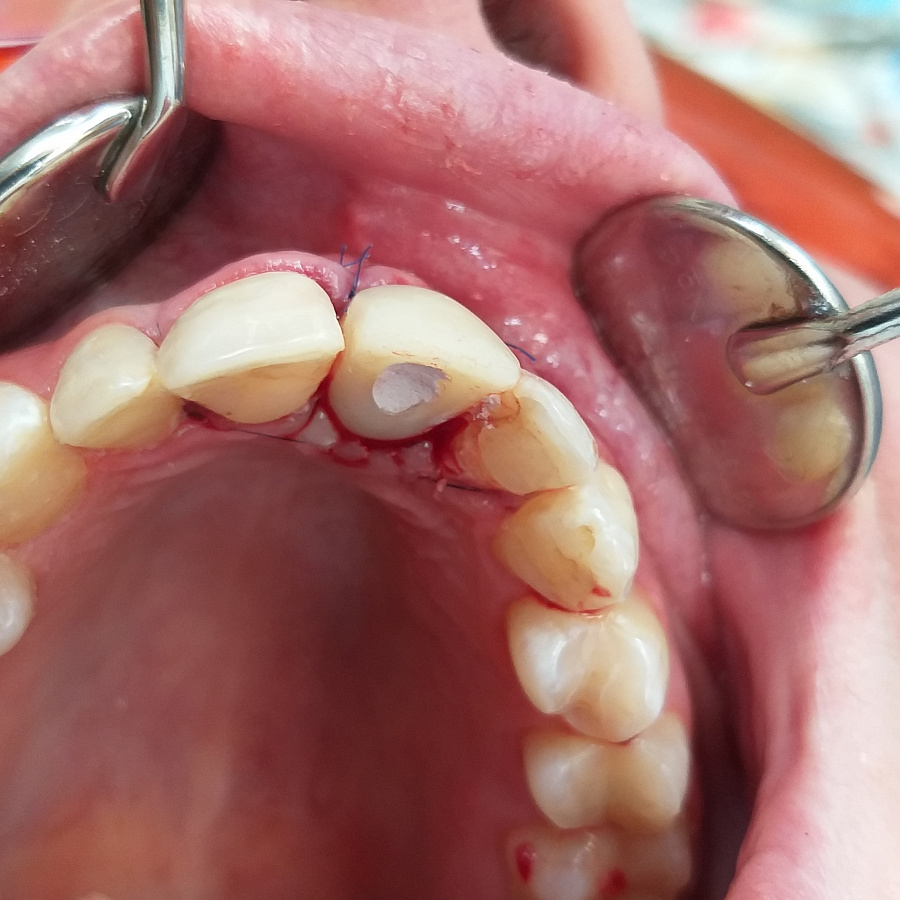

Пациентка обратилась в клинику с жалобами на воспаление десны в области переднего зуба верхней челюсти, необычный вид десны, кровоточивость десны во время чистки зубов.

Поставлен диагноз посттравматическая резорбция корня.

Был предложен вариант одномоментной имплантации (удаление зуба и установка импланта за одно посещение).

Следующий этап после удаления разрушенного корня и установки зубного имплантата - восстановление косметического дефекта временной коронкой, изготовленной после операции.